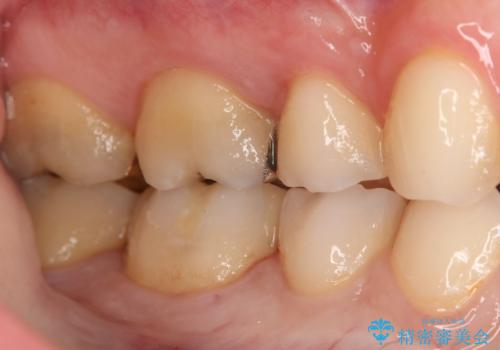

- 右下6・7番の虫歯治療を主訴に来院された患者様です。

精度が高く見た目が良いものを希望されたので、切削量・形態を考慮しセラミックインレーでの治療を計画しました。

奥歯でも下の歯の場合は審美性の高いセラミックを選択される患者様が多いです。